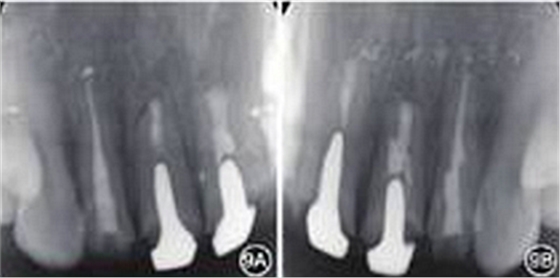

图9 6个月复查患者根尖X线片 A:根尖病变愈合;B:根尖病变接近愈合